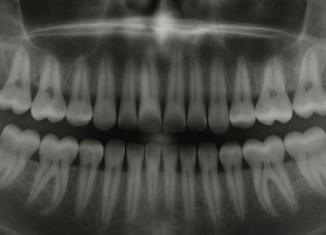

داهێنانەکا یابانی یا مێژوویی دوارێ چارەسەریا ددانان دا

زانایێن یابانی دەرمانەک داهێنا کو ب رێیا وی د شیان دایە ددانێن مرۆڤان وەکو بەرێ نوو ببنەڤە.

ئەڤ دەرمانێ زانایێن یابانی ب سەرکێێشیا دکتور کاتسو...